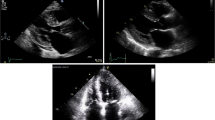

The diagnosis is defined by a septal-to-posterior diastolic wall thickness ratio ≥ 1.3 [9] (or ≥1.5 in hypertensive patients) (Fig. 2A).

a PLAX view demonstrating the asymmetrical hypertrophy of the interventricular septum over the posterior wall with a ratio >1.3. b Massive septal hypertrophy characterized by a septal diastolic thickness > 30 mm. c Massive septal hypertrophy with RVOT obstruction by the projection of the massively hypertrophied interventricular septum into the right outflow tract. d MOHC with the ‘hourglass’ shaped left ventricle consisting of two different chambers: the proximal and the distal chamber

It corresponds to reverse curvature and sigmoid septum of Syed’s classification [50].

Massive septal hypertrophy

It is a rare HCM phenotype characterized by a septal diastolic thickness ≥ 30 mm (Fig. 2B). It is usually associated with a LVOTO but a RVOT obstruction may also occur with the projection of the massively hypertrophied interventricular septum into the right outflow tract (Fig. 2C). This pattern is associated with an higher risk of arrhythmic sudden death [1].

Midventricular Obstructive Hypertrophic Cardiomyopathy (MOHC)

It is characterized by an atypical intraluminal stenosis of the left ventricle. Hypertrophy is detectable only in the mid portion of the left ventricle and involves the papillary muscles, resulting in a systolic obstruction of the mid-ventricle (Fig. 2D).

The ‘hourglass’ shaped left ventricle consists of two different chambers: the proximal and the distal chamber. The proximal chamber is an enlarged cavity, with thinned walls and an inferior-basal septum bulging (Fig. 2D). The distal chamber usually is an apical aneurism.